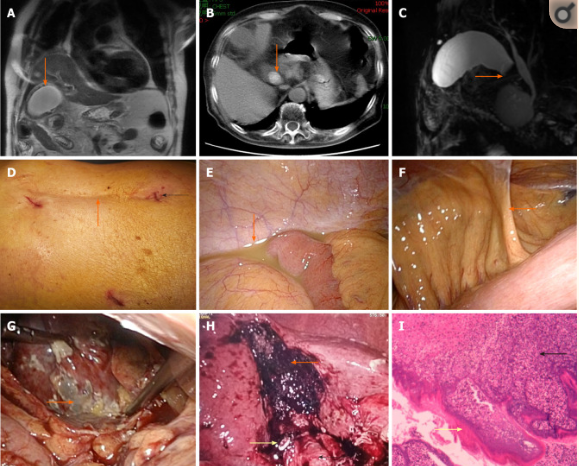

查体发现右上腹压痛,反跳痛明显,墨菲征阳性,无移动性浊音,血压:86/56mmHg,脉搏:110次/分,R:28次/分。白细胞计数(WBC)16.2x109/L,中性粒细胞比例92.4%,C反应蛋白178.01mg/L,血清降钙素原1.31ng/mL,谷丙转氨酶19U/mL,白蛋白38.1g/L,总胆红素36.76μmol/L,直接胆红素为10.53μmol/L,肌钙蛋白0.009ng/mL,B型利钠肽(BNP)为348.9pg/mL,血气分析表明,氧分压为85.1mmHg,氧饱和度96.7%,二氧化碳分压25.3mmHg。胸腹部CT提示肺部感染,磁共振成像(MRI)显示胆囊壁增厚,周围有渗出,如图1A,胆囊颈部可见直径约2cm的高信号影,如图1B,磁共振胰胆管造影提示胆囊颈充盈缺损,如图1C。

图1 A胆囊壁增厚,周围有渗出,B胆囊颈部可见直径约2cm的高信号影,C磁共振胰胆管造影提示胆囊颈充盈缺损,D腹腔镜戳卡口位置,E腹部脓性积液,F右上腹炎性粘连,G胆囊壁坏疽,H:胆囊床创面,胆囊管夹闭,I:术后病理提示中性粒细胞浸润

患者术前安排隔离病房,行抗炎及对症治疗,停用阿司匹林,积极准备手术,术中见患者腹腔脓性积液,如图1E,右上腹粘连较重,胆囊壁坏疽,如图1G,胆囊腔内有化脓性胆汁,胆囊颈部结石坎顿,遂行腹腔镜胆囊切除术,手术持续110分钟,术中出血100ml。术后患者气管插管状态下返回隔离病房,16小时后,脱离呼吸机,拔除气管导管,术后8天患者康复出院。